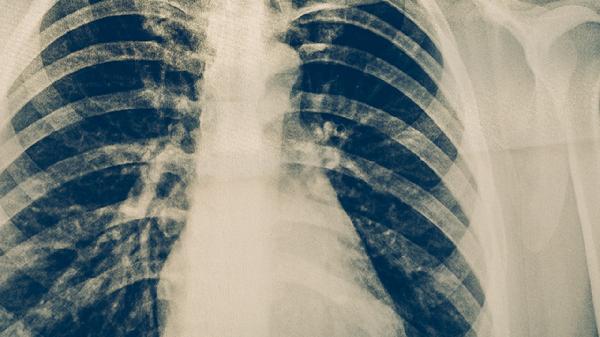

肺結(jié)核的藥物治療需遵醫(yī)囑規(guī)范使用抗結(jié)核藥物,常用藥物包括異煙肼片、利福平膠囊、吡嗪酰胺片、乙胺丁醇片和鏈霉素注射液等。肺結(jié)核是由結(jié)核分枝桿菌感染引起的慢性傳染病,藥物治療需遵循早期、聯(lián)合、適量、規(guī)律和全程的原則。

肺結(jié)核患者除規(guī)范用藥外,需保證充足營(yíng)養(yǎng)攝入,適當(dāng)增加優(yōu)質(zhì)蛋白和維生素豐富的食物。治療期間應(yīng)單獨(dú)居住,保持居室通風(fēng),避免隨地吐痰。嚴(yán)格遵醫(yī)囑完成6-9個(gè)月的全療程治療,不可自行停藥或減量。定期復(fù)查胸部影像學(xué)和痰結(jié)核菌檢查,評(píng)估治療效果。出現(xiàn)藥物不良反應(yīng)時(shí)應(yīng)及時(shí)就醫(yī)調(diào)整方案,不可擅自處理。完成治療后仍需定期隨訪,監(jiān)測(cè)復(fù)發(fā)可能。